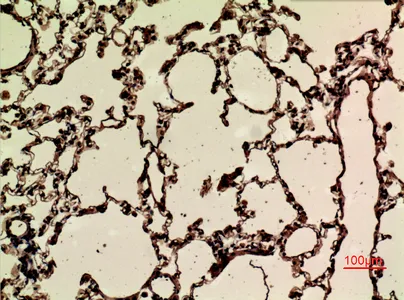

CD68 Rabbit Polyclonal Antibody

Cat: APRab08436

Size1:50μl Price1:$118

Size2:100μl Price2:$220

Size3:500μl Price3:$980

Size2:100μl Price2:$220

Size3:500μl Price3:$980